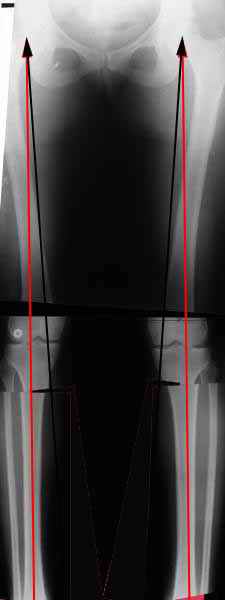

Вот, с учетом и без учета, и на разных уровнях...

AC> Вот, с учетом и без учета, и на разных уровнях...

Из приведнной схемы не совсеим понял что означают разноцветные линии.

И зачем латерализация периферического фрагмента. Я всегда делаю медиализацию. См схему. И для данного случая медиализация подходит как нельзя лучше.

a> Из приведнной схемы не совсеим понял что означают разноцветные линии.

Черные - это нынешняя механическая ось. Красные - это планируемая правильная ось.

a> И зачем латерализация периферического фрагмента.

;-) Читайте Палея. Стр. 114-115.

a> Я всегда делаю медиализацию. См схему. И для данного случая

Медиализация - это чисто эстетический прием, как я понимаю. Поскольку если делать остеотомию ниже вершины деформации, для восстановления оси надо делать смещение по ширине, в данном случае как раз латерализацию.